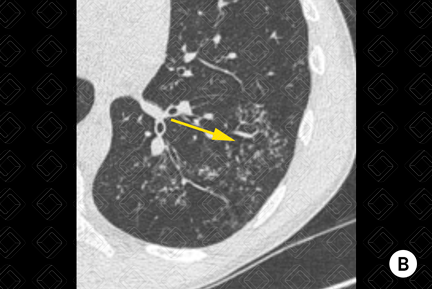

Descrição das figuras 1, 2 e 3: Adolescente de 16 anos, com desconforto respiratório e febre. Imagem A (figura 1): radiografia de tórax evidencia moderado derrame pleural (asterisco). Imagem B (figuras 2 e 3): exame foi complementado com tomografia de tórax com contraste, pela não melhora clínica. Observa-se o derrame pleural (seta vermelha) à direita e os nódulos centrolobulares (seta amarela) com padrão de árvore em brotamento à esquerda, achados muito sugestivos de tuberculose pulmonar, confirmada posteriormente.

• Tomografia computadorizada (TC) do tórax : Em geral, é usado somente nos casos mais graves, como suspeitas de neoplasia, complicação de derrame parapneumônico ou quando a causa do derrame pleural permanece desconhecida. Em geral, a densidade do derrame pleural na TC encontra-se entre 10-20 UH (densidade líquida). Figuras 1 e 2;